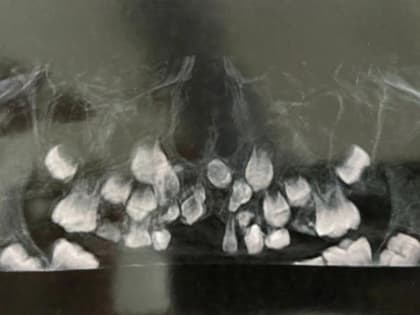

Врачи в Ростове помогли школьнику, у которого в восемь лет не росли зубы

Фото: pxhere.com Врачи помогли 8-летнему мальчику, у которого из-за редкой патологии не росли зубы, рассказали в Минздраве Ростовской области.